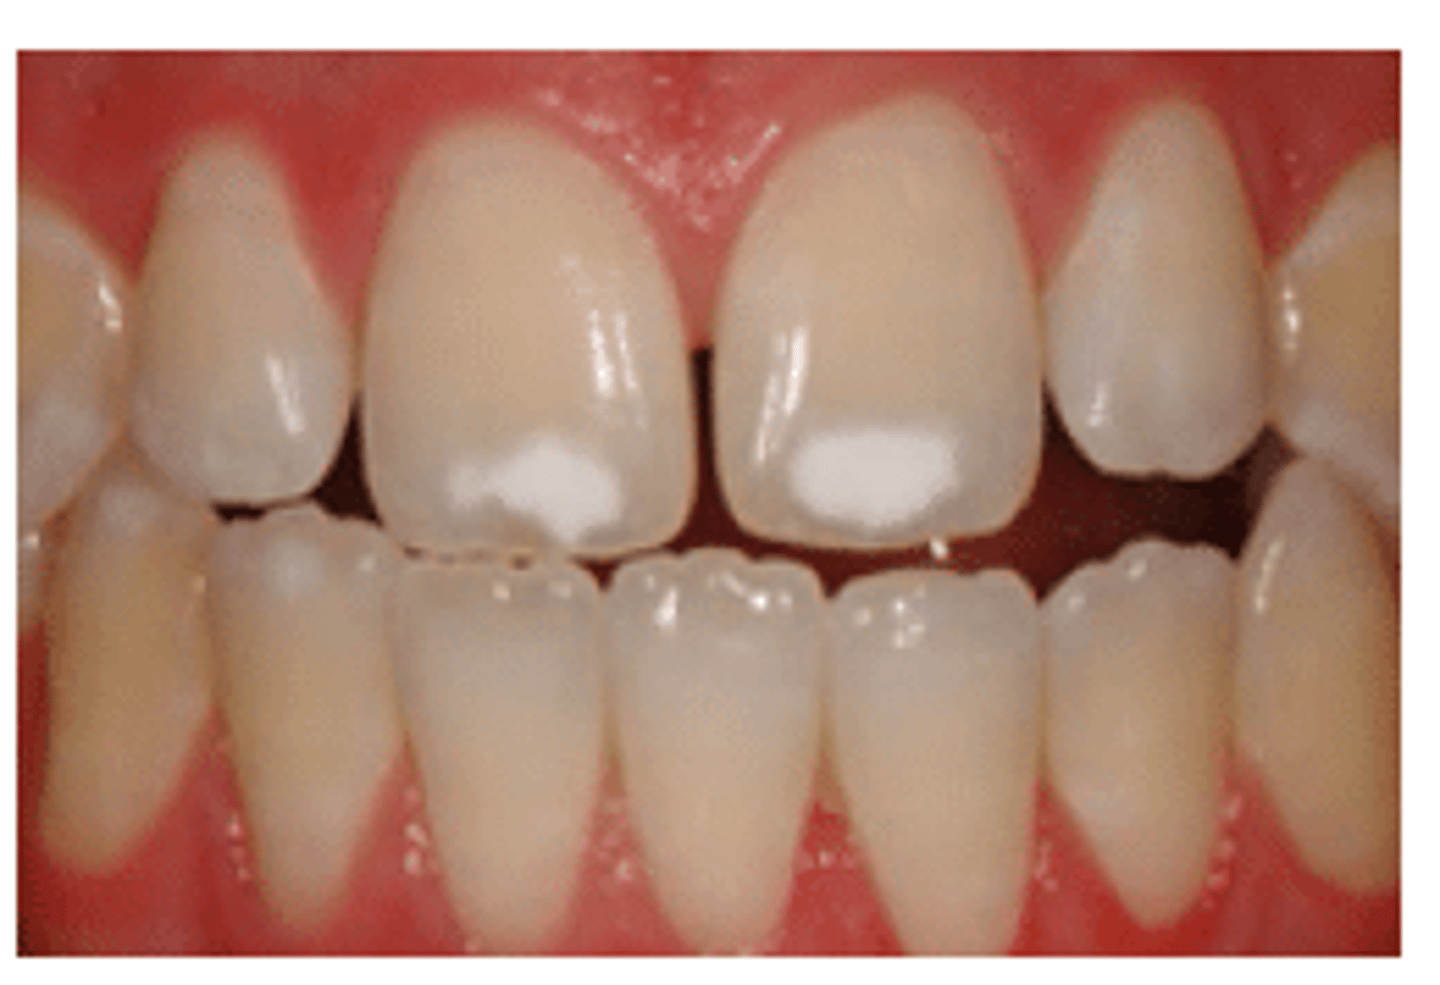

White spot lesions

First sign of caries

early sign

White Spot Lesions are an ____ ____ of Caries

-Surface layer with mineral content lower than sound enamel

- Higher mineral content than underlying body of lesion